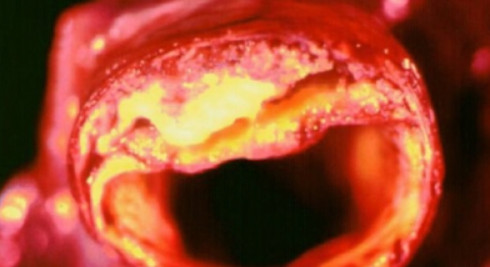

고혈압 수치가 높은것만으로도 위험하지만 합병증까지 생긴다면 더 심각합니다. 합병증이 오면 심할 경우 생명의 위협까지 가할 수 있어 관리가 아주 중요합니다. 고혈압은 뇌에 영향을 주어 뇌출혈, 뇌경색, 치매를 유발할 수 있습니다. 또한 눈에도 영향을 주어 망막증이나 심하게는 실명까지 갈 수 있고 심장에도 무리를 주어 협심증, 신부전, 심근경색까지 발생할 수 있습니다.